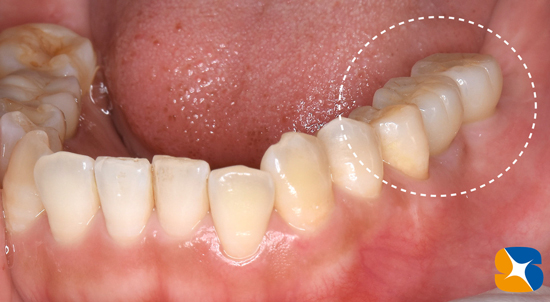

左下のインプラント予定部。

切開して開けてみると、2ヶ月前の抜歯跡が見受けられた。しかし

当院では骨の再生治療をインプラント移植時に同時進行で施しているので、全く問題はありません。

骨のない所に人工骨のβ–TCPを添加して、本物の骨に置換するのを待ちます。

左下の施術終了。